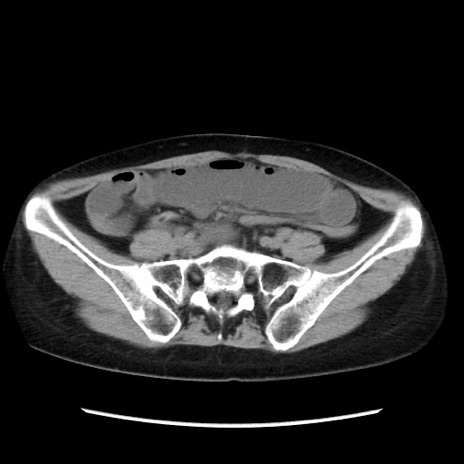

症例32(横断像)

【症例】40歳代 女性

【主訴】上腹部痛、嘔気・嘔吐

【現病歴】約9時間前頃から急に上腹部痛、嘔気、嘔吐が出現。改善しないため救急要請。

【既往歴】子宮頚癌(広汎子宮全摘術、放射線療法)、腸閉塞

【身体所見】腹部:平坦、軟、腸雑音亢進、上腹部を中心に腹部全体に圧痛あり。

【データ】WBC 8400、CRP 0.03